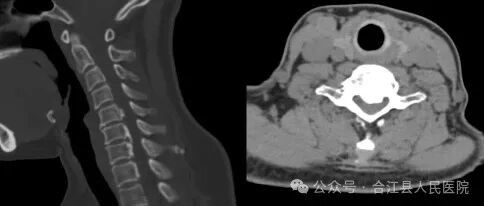

近日,我院脊柱外科为一名颈椎后纵韧带骨化(OPLL)伴椎管重度狭窄颈椎病患者成功实施了经前路颈5、6椎体次全切、后纵韧带骨化骨切除、椎管减压、钛网支撑植骨、前路钢板内固定术。

术前

入院后完善颈椎X线片、CT、核磁共振、血生化等各项检查,诊断为颈椎后纵韧带骨化(OPLL)伴重度颈椎管狭窄、脊髓型+神经根混合型颈椎病。

图片

术后